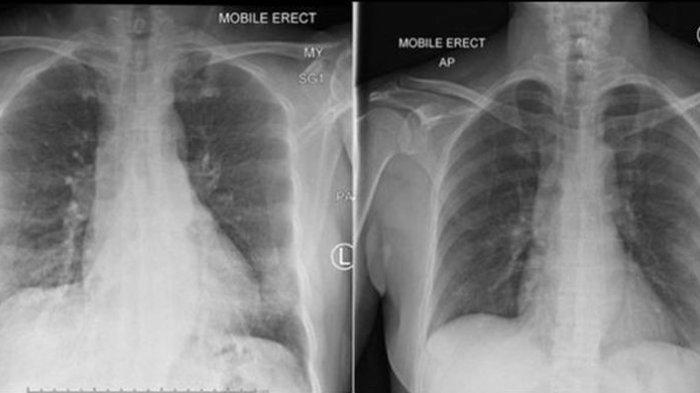

Peneliti mengungkapkan penemuan baru dari paru-paru pasien yang sudah berhasil sembuh.